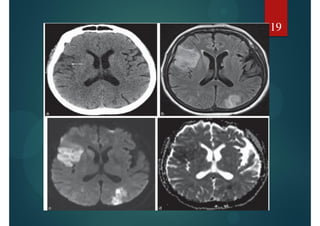

AVC ischémique : IRM

Avant 6 heures, les séquences classiques T1 et T2 sont normales. Ce

n'est qu'à partir de 48 heures que les séquences

conventionnelles T1 et T2 deviennent positives (hyposignal

T1, hypersignal T2).

La diffusion est positive de quelques minutes après le

début des symptômes jusqu'à 9 jours sous forme d'un

hypersignal diffusion

18